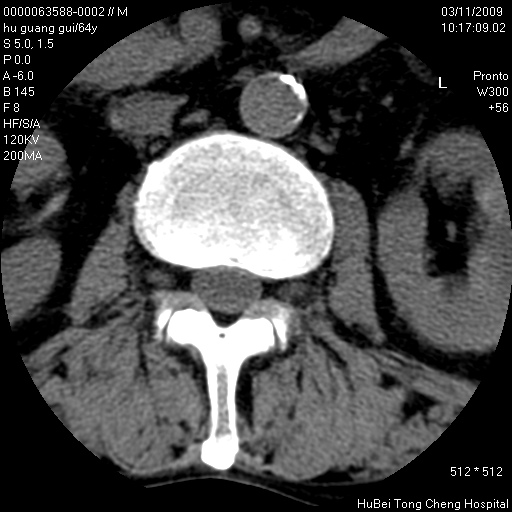

患者 男,64岁。腰痛十余天。(临床未提供其他病史)

临床诊断:腰痛原因待查(腰椎间盘突出症?)。

腰椎间盘ct轴位平扫(层厚5mm,层距4mm),图像如下:

腰椎退行性变,腰4—5椎间盘膨出。

右侧骶骨侧块骨侵蚀,骶髂关节骨性关节面破坏,并见软组织肿块,考虑骨转移瘤可能,进一步检查。

1.腰椎退行性变,腰4—5椎间盘膨出。

2.右侧骶骨侧块骨侵蚀,骶髂关节骨性关节面破坏,并见软组织肿块,考虑:脊索瘤,骨转移瘤可能,进一步检查。

1)腰椎退行性变,l4—5椎间盘膨出。2)骶骨右侧块骨转移瘤可能,3)水平骶椎。建议作一步检查。